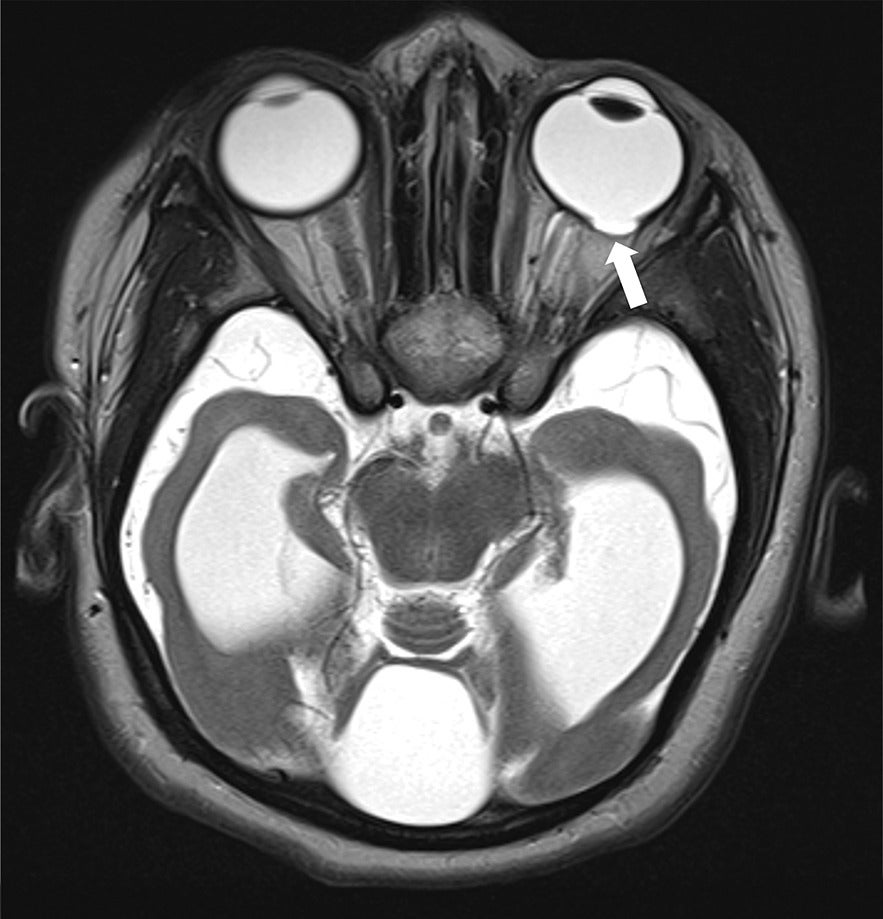

An MRI of the brain ( Figure 1 ) performed at 5 years of age demonstrated severe microcephaly with a markedly diffuse supratentorial simplified gyral pattern. There was incomplete/impaired myelination throughout the parieto-occipital and temporal lobes and subcortical white matter of the frontal lobes bilaterally. Severe global supratentorial white matter volume reduction was seen along with diffuse thinning and apparent foreshortening of the small corpus callosum, predominantly posteriorly. The bilateral lateral and third ventricles were markedly enlarged, while the fourth ventricle was moderately enlarged. The cerebellum appeared diffusely hypoplastic. Furthermore, there was a significantly enlarged mega cisterna magna, which appeared to communicate with the fourth ventricle while rotating and pushing the vermis upward, resulting in a moderately elevated tegmento-vermian angle of 24 degrees. The pons was severely hypoplastic, and the pontine belly is completely missing with an apparent flat ventral pontine surface. In addition, scattered peripheral parenchymal calcifications were seen ( Figure 2 ). Lastly, there was a mid-sized coloboma along the posterolateral left eye globe in the region of the macula measuring approximately 0.6 cm in diameter ( Figure 3 ). Both optic nerves appeared thinned with a maximal cross-sectional diameter of 1.4 mm.

Axial T2 brain MRI demonstrating a chorioretinal coloboma (arrow) located in the posterolateral aspect of the left orbit as well as mild bilateral optic nerve atrophy (right optic nerve not shown).